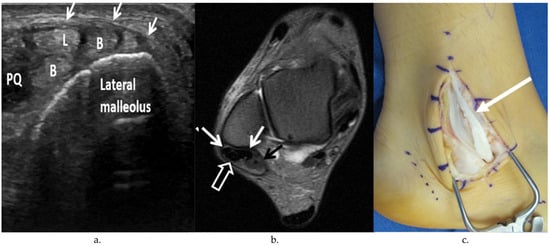

4.1. Peroneus Brevis Tear